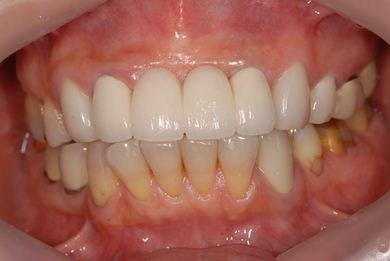

治療前

• 治療前

治療後

• 治療後